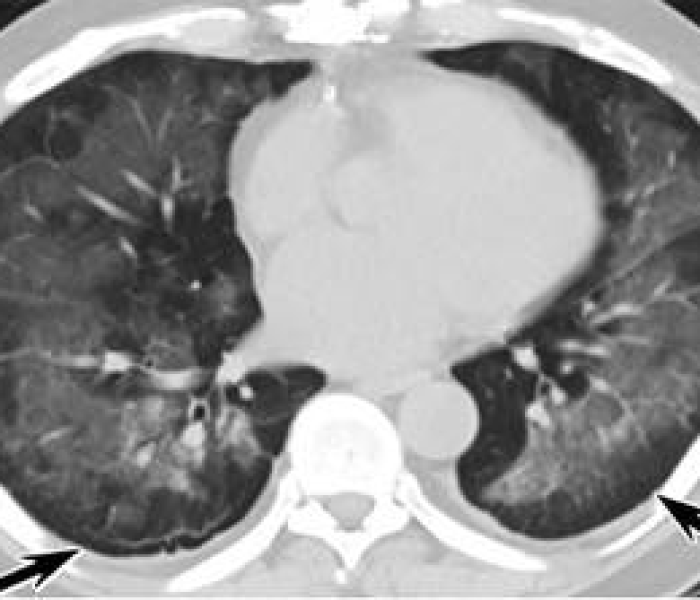

引言:数字背后的全球疫情新阶段世界卫生组织最新数据显示,中国境外新冠肺炎确诊病例已达12668例,覆盖超过70个国家和地区,这一数字不仅标志着疫情进入全球扩散的新阶段,更凸显了人类命运共同体在公共...